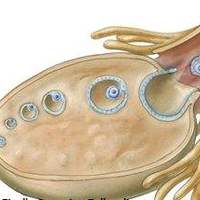

存在卵巢过早衰老、多囊卵巢综合征,以及肾上腺皮质功能、甲状腺皮质功能,以及脑垂体功能、下丘脑脑功能等异样的病人,卵巢中卵泡数目就会数量少。对在这方面片面患者是可以做试管婴儿促排的,终究卵泡数量未几会导致自然怀孕成功率降低,而试管婴儿促排的目的就是使用药物刺激女性卵巢,以增加卵巢中卵泡的数目,从而提升受孕概率。其次试管婴儿促排还能促使女性卵巢中多个卵泡相继成长发育,直至发育成熟即B超监测下卵泡大小在18-22mm之间,进而就能够取出多个成熟卵泡用于与精子进行受精,进而提高怀孕概率。